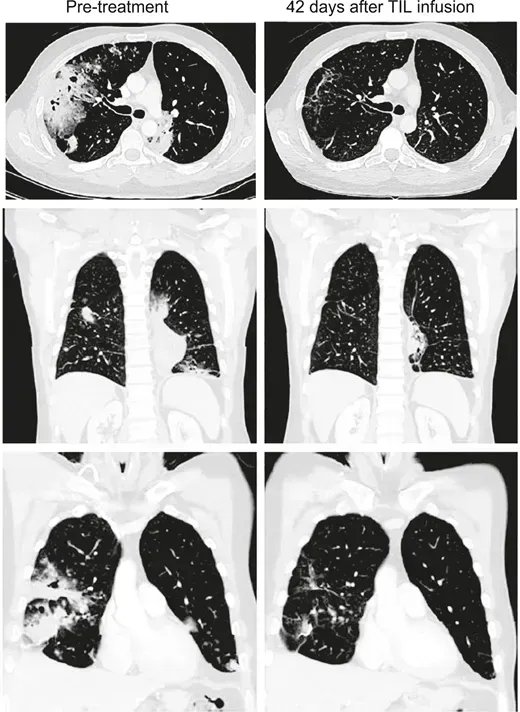

患者3

患者3是一位患有转移性鳞状细胞癌的女性,此前接受过多线治疗,包括顺铂+长春新碱+博来霉素诱导化疗、吉西他滨+顺铂放化疗,后续出现气管旁、隆突下及双侧肺门淋巴结转移,经拓扑替康+紫杉醇治疗后病情仍进展,治疗时肿瘤已转移至腹主动脉旁、双侧肺门、隆突下及髂淋巴结。接受HPV-TIL治疗后,所有病灶完全消退(详见下图A、C),治疗后22个月无疾病复发。

▲图源“JCO”,版权归原作者所有,如无意中侵犯了知识产权,请联系我们删除

患者6

患者6是一位转移性腺癌女性,原发肿瘤对放化疗耐药,挽救性手术发现腹主动脉旁、髂淋巴结及盆腔其他部位受累,后续癌症进展至腹膜后淋巴结、肝脏表面,伴右侧输尿管肾积水及双侧肺栓塞,需放置输尿管支架并抗凝治疗。治疗时腹膜后、腹壁、结肠旁、肝旁及盆腔均有进展性肿瘤,HPV-TIL治疗后获得完全临床缓解(CR,详见下图B、D),治疗后15个月无疾病复发迹象,右侧输尿管肿瘤消退后已取出输尿管支架。

综上,单次输注HPV-TILs可使转移性宫颈癌实现持久、完全的肿瘤消退,为这类化疗难治性患者提供了新的治疗方向。